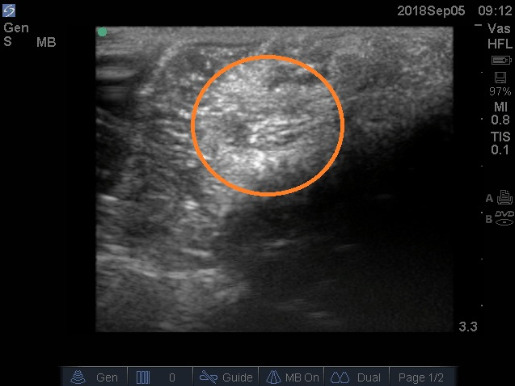

The mass was photographed in situ (i.e., in it its original position) from various angles, and imaged using 13-6 MHz ultrasound transducer powered by Sonosite M-Turbo Ultrasound machine (FuJIFILMS Sonosite, Inc). The ultrasound images confirmed the round outline of the mass with no evidence of fluid inside (Figure 3).